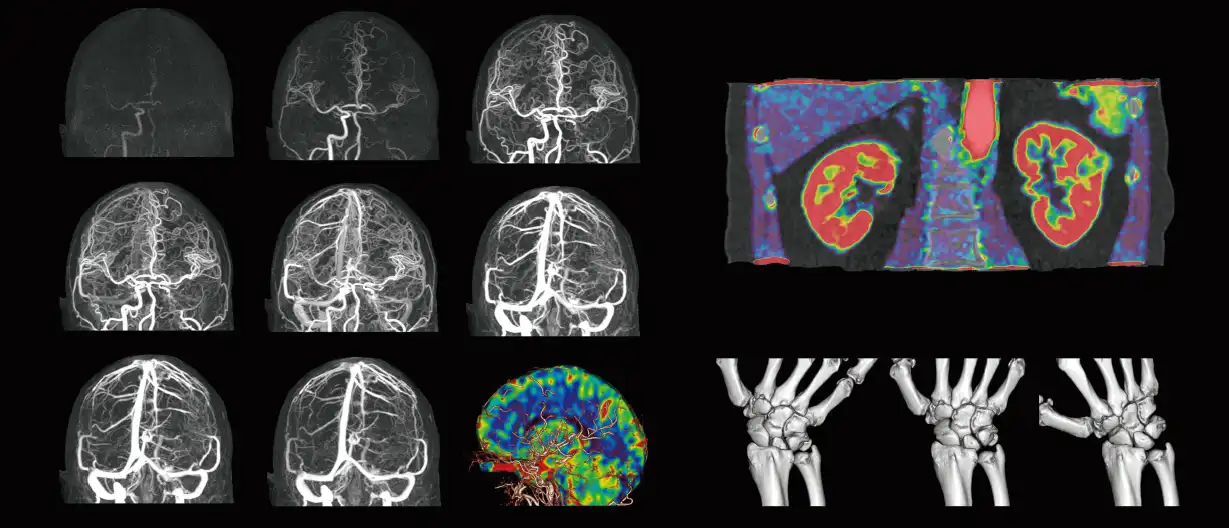

Aquilion ONE™ / GENESIS Edition goes beyond the evolution of dynamic volume CT. Intensive clinically focused research and breakthrough technological developments have culminated in a CT system with industry-leading spatial resolution and reduced radiation dose requirements.

GENESIS Edition’s 16 cm wide area detector signicantly improves your ability to obtain high-quality images for routine and advanced studies. One rotation is all it takes to acquire a whole heart, a neonatal chest, a foot or an ankle exam – in a fraction of a second with less dose and great z-axis uniformity.

Adding dynamic functional imaging to morphology can provide valuable further insights, helping you to optimize disease management and treatment plans. Advanced perfusion maps can assist in diagnosis and therapy response verification of stroke or tumors, while dynamic joint studies help identify causes of pain or immobility.